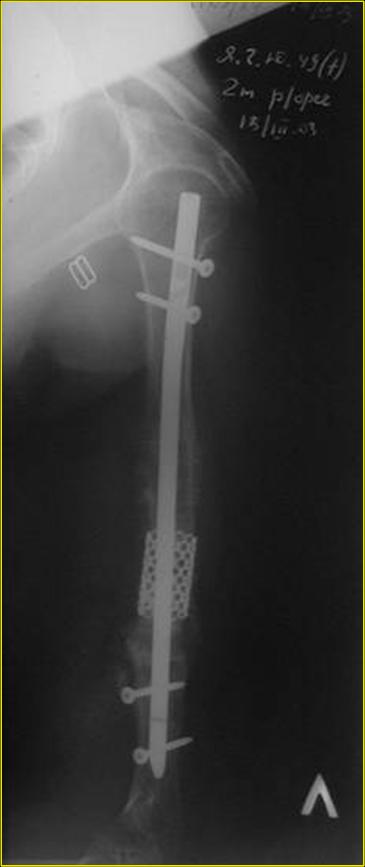

Рентгеновская версия реконструкции. хронология:

после операции, 2 мес. после операции, через 1 год

Движения в полном объеме восстановлены к 2 мес. после операции. Если надо могу показать мультик. Сейчас уже прошло более 3 лет, больная не

показывается. Успехов ЛАФ.